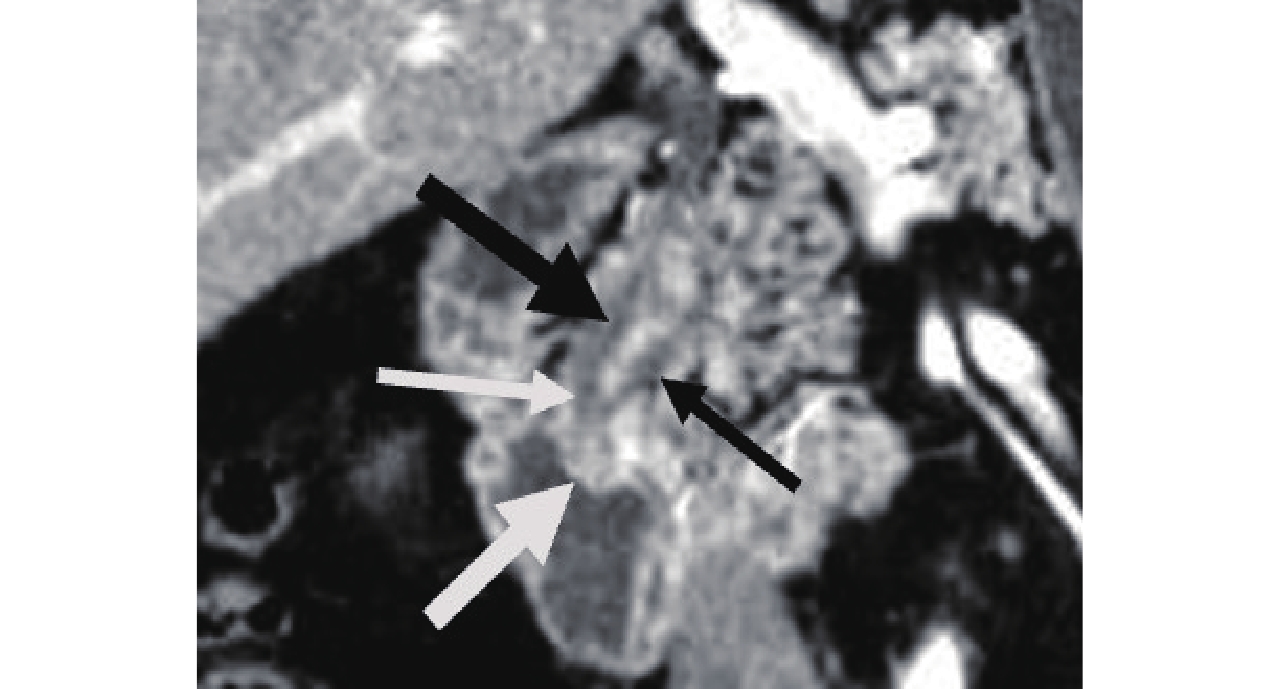

![]() 图 2 CPR显示正常壶腹部,胆总管(粗黑箭头)与主胰管(细黑箭头)汇合成肝胰壶腹(细白箭头),突入十二指肠降段下1/3内侧壁,形成十二指肠大乳头(粗白箭头)Figure 2. CPR shows the normal ampulla, the common bile duct (thick black arrow) and the main pancreatic duct (thin black arrow) converging to form Vater's ampulla (thin white arrow), which protrudes into the medial wall of the lower 1/3 of the descending duodenum to form duodenal papilla (thick white arrow)

图 2 CPR显示正常壶腹部,胆总管(粗黑箭头)与主胰管(细黑箭头)汇合成肝胰壶腹(细白箭头),突入十二指肠降段下1/3内侧壁,形成十二指肠大乳头(粗白箭头)Figure 2. CPR shows the normal ampulla, the common bile duct (thick black arrow) and the main pancreatic duct (thin black arrow) converging to form Vater's ampulla (thin white arrow), which protrudes into the medial wall of the lower 1/3 of the descending duodenum to form duodenal papilla (thick white arrow)2.2 十二指肠乳头癌影像表现

图 2 CPR显示正常壶腹部,胆总管(粗黑箭头)与主胰管(细黑箭头)汇合成肝胰壶腹(细白箭头),突入十二指肠降段下1/3内侧壁,形成十二指肠大乳头(粗白箭头)

Figure 2. CPR shows the normal ampulla, the common bile duct (thick black arrow) and the main pancreatic duct (thin black arrow) converging to form Vater's ampulla (thin white arrow), which protrudes into the medial wall of the lower 1/3 of the descending duodenum to form duodenal papilla (thick white arrow)